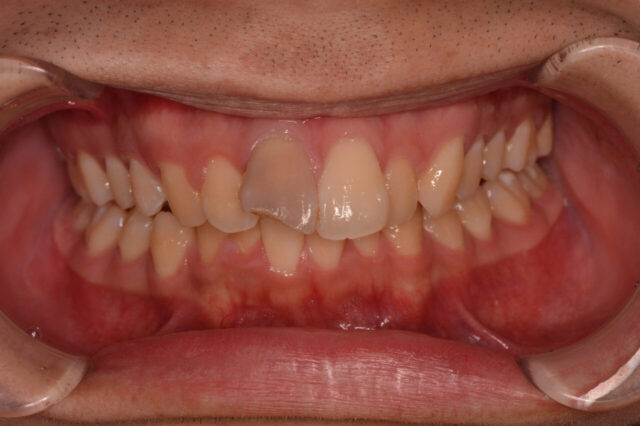

インプラントを使用せず、自家歯牙移植による全顎的な機能回復

before

after

主訴 「全体的にしっかりと噛めるようになりたい。あわせて、前歯の形態・色彩を整えたい」とお悩みで、福岡市西区・姪浜エリアからご来院された患者様の症例です。他院では複数の抜歯とインプラントを提案されたものの、「可能な限り天然歯を保存したい」との強いご希望がありました。 治療 治療内容:自家組織を活用した包括的歯科治療(フルマウス)

当院では、福岡市西区・姪浜周辺で精密な歯科治療をお探しの方へ、一口腔単位の健康を考慮した全顎的な咬合構成(フルマウス治療)を提案しています。

精密検査と包括的診断: 歯科用CT、口腔内写真、模型診査、および咬合分析を実施。噛み合わせが崩れた根本原因を特定し、長期的な予後を見据えた治療計画を策定しました。

インプラント以外の選択肢「自家歯移植」: 保存不可能な部位に対し、ご自身の歯を活用した「自家歯移植」を適応しました。インプラント以外の選択肢として、歯根膜組織を維持したまま移植を行うことで、天然歯に近い生理的な咬合感覚の再現を図っています。

歯内療法および初期治療: 温存可能な残存歯については、マイクロスコープを用いた精密な根管治療虫歯治療および歯周病治療を行い、基礎となる天然歯の保存に努めました。

審美補綴(セラミックス治療): 最終補綴物として、生体親和性が高くプラークの付着しにくいオールセラミックスを採用。機能的な咬合の再構築とともに、自然で美しい口元の回復を行いました。料金 補綴治療(1本あたり)→16万円+ TAX

歯牙移植→保険適応

備考 自家歯移植の意義: 自家組織を利用するため拒絶反応が少なく、歯根膜による緩衝能(クッション性)を保持できることが最大の利点です。

地域に根ざした高度治療: 福岡市西区や姪浜にお住まいの、インプラントに抵抗がある方や、ご自身の歯を大切にしたい方にとって、移植は有効な選択肢の一つとなります。

リスク・副作用: 自家歯移植は、移植後の歯根吸収や脱落のリスクがゼロではありません。また、セラミックスは過度な衝撃により破折する可能性があります